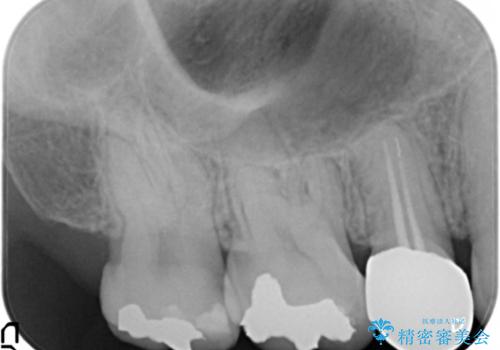

- 低予算で銀歯を白くしたいとご希望し来院された患者様です。

右上小臼歯(右上5)はオールセラミッククラウン(e-max press)、下顎臼歯(下顎両側67)はメタルボンドクラウンによりやりかえることにしました。

再根管治療はご希望されず、行っておりません。

右上小臼歯(右上5):オールセラミッククラウン エコノミー

下顎両側臼歯(下顎両側67):メタルボンドクラウン エコノミー